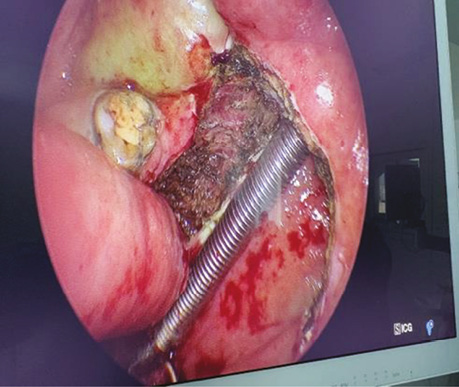

Пацієнт В., 40 років. Встановлено діагноз — плоскоклітинна карцинома м’якого піднебіння T2N0M0. Проведено трансоральну CO₂-лазерну резекцію м’якого піднебіння. Етапи хірургічного втручання представлені на рис. 1–2.

Рис. 1. Трансоральна CO₂-лазерна резекція м’якого піднебіння із попередньою візуалізацією зони ураження за допомогою індоціанінового зеленого барвника (ICG) для точнішого визначення меж пухлинного ураження